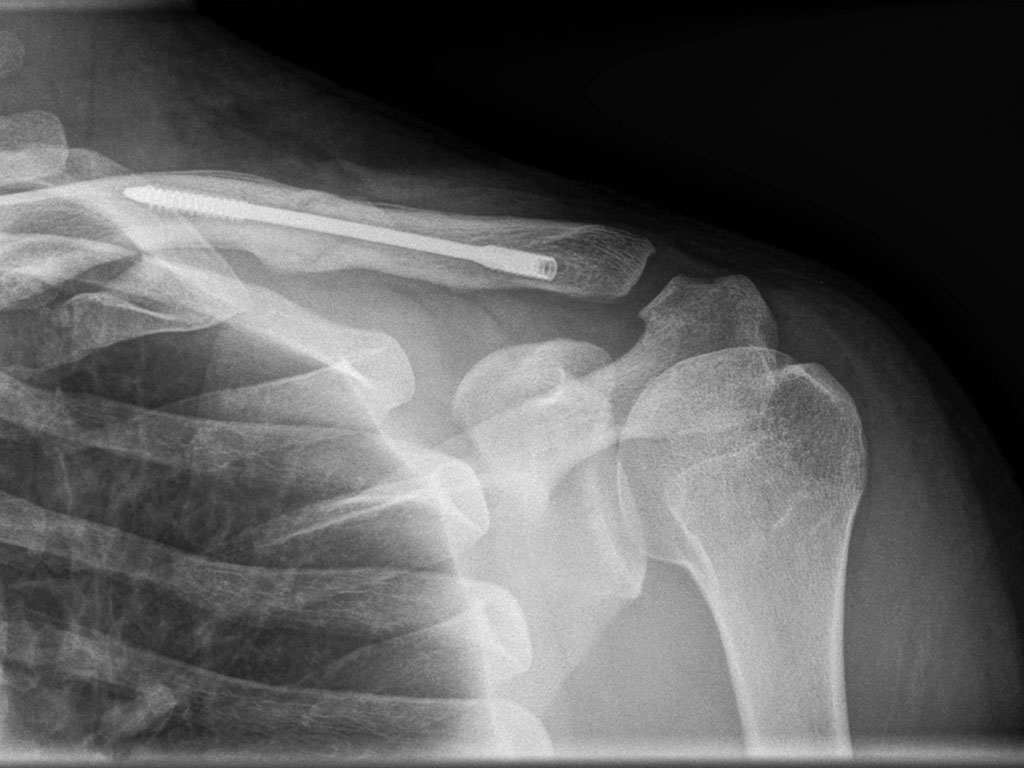

Dual-Trak Clavicle Screw System

The Acumed Dual-Trak Clavicle Screw System is a fully intramedullary solution for simple middle third clavicle fractures.

Intramedullary Clavicle Fixation

An alternative to clavicle plating, the system is designed to reduce prominent implant hardware and soft tissue irritation.